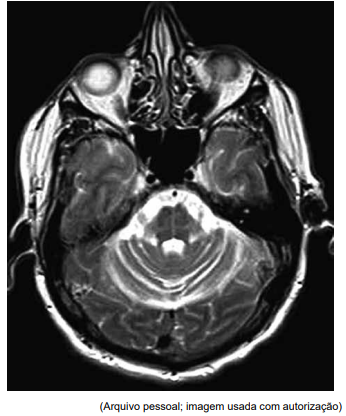

Homem de 56 anos apresenta quadro de tremor de repouso bilateral nos membros superiores há seis meses. Ao exame físico, apresentava tremor de repouso bilateral de frequência moderada, ligeiramente mais acentuado no membro superior direito do que no esquerdo, e rigidez em roda dentada bilateral, que parecia ser igual em ambos os membros; bradicinesia significativa que afeta ambos os lados do corpo. Foi-lhe prescrita levodopa, que teve pouco efeito sobre os sintomas. No acompanhamento, um ano depois, ele relata instabilidade significativa na marcha. Nesse momento, o exame mostra dismetria bilateral, e sua marcha é ampla e ligeiramente cambaleante. Uma ressonância magnética (imagem axial ponderada em T2) é realizada e mostrada a seguir: